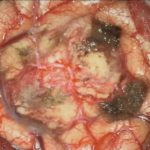

706

'25年12月

80代

右頭頂葉腫瘍

頭蓋内腫瘍摘出術

No.’25_108 摘出 前

No.’25_108  摘出 中

No.’25_108 摘出 後